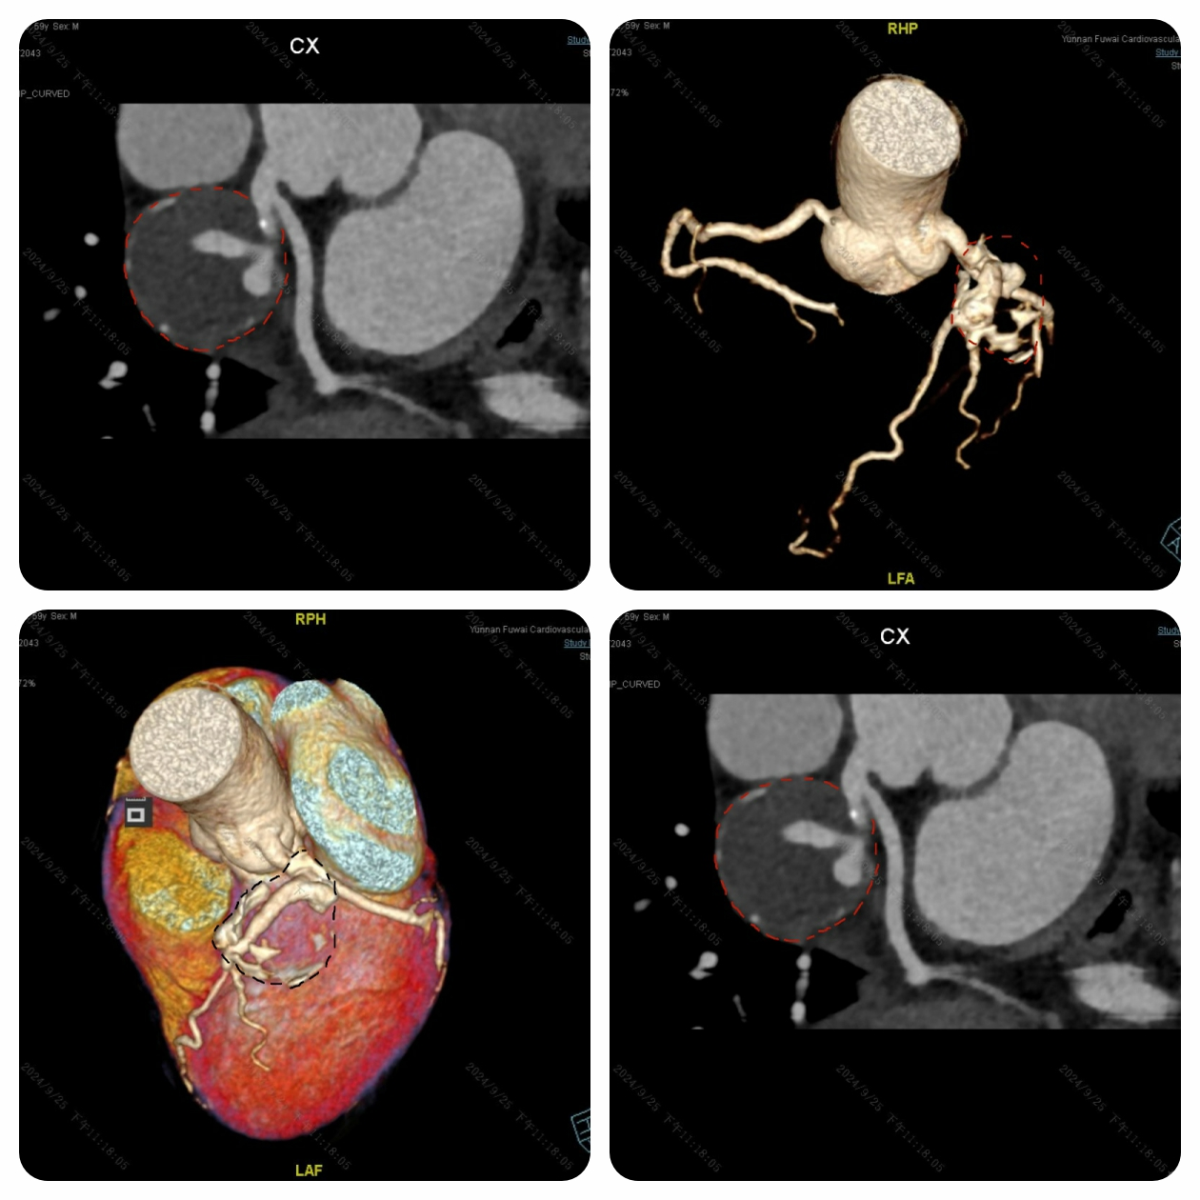

59 岁的老秦(化名),被高血压、高血脂困扰了 10 多年。因不明原因的心慌,他来到云南省阜外医院。入院前一个月左右,老秦时常感觉心慌得厉害,心慌时还伴有头晕症状,每次心慌持续几分钟后自行缓解,好在未曾出现胸口疼痛、晕厥等情况。鉴于老秦的年龄较大,我们为他安排了冠状动脉 CT 检查。这不查不知道,一查吓一跳,老秦的心脏表面竟冒出了一个 “大地雷”。仔细查看,这个 “大地雷” 紧紧包裹着左侧冠状动脉中最重要的血管 —— 前降支。更糟糕的是,“地雷” 内的血液已经凝固成血栓,表面还形成了一层钙化的 “铠甲”,仿佛一颗随时可能引爆的 “定时炸弹”。

为了确定是否需要为老秦实施外科手术 “排雷”,我们紧接着安排了冠状动脉造影检查。结果显示,虽然冠状动脉前降支被 “地雷” 包裹,但血管腔依旧通畅,“地雷” 没有对冠状动脉造成压迫,血管内的血液也没有渗漏到 “地雷” 内。

经过手术专家们的深入讨论,一致认定老秦心脏上的 “地雷” 属于冠状动脉假性动脉瘤。由于 “地雷” 没有压迫冠状动脉,血液没有外溢,且表面有 “铠甲” 保护,内部又是实心血栓,爆炸风险相对较低。综合考虑老秦的意见后,专家团队决定暂不进行外科 “排雷”,而是建议他定期复查,密切关注 “地雷” 的动态。